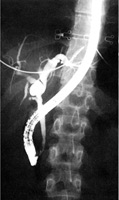

Η MRCP απεικονίζει με αρκετή ακρίβεια το χοληφόρο και παγκρεατικό δένδρο και

είναι εξέταση που προτιμάται σε παιδιά. Η ERCP είναι επεμβατική μέθοδος, προϋποθέτει

μεγάλη εμπειρία, ιδίως στην εφαρμογή της στα παιδιά και έχει αυξημένες πιθανότητες

επιπλοκών (αιμορραγίας ή παγκρεατίτιδας) (εικόνα 7).

EIKONA 7.

Πάγκρεας. MRCP. Κύστεις χοληδόχου και παγκρεατικού πόρου.

Πάγκρεας MRCP. Διάταση παγκρεατικού πόρου.

Πάγκρεας ERCP